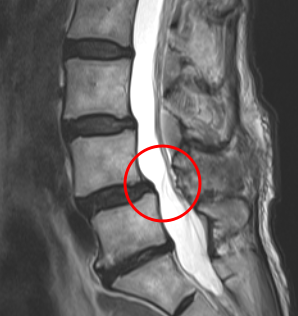

治療後

手術の翌日には、座っていると少し痛みが出るものの、これまであった左足の痛みはなくなったそうです。さらに術後1か月目には腰痛は10から2に、足の痛みは10から0になりました。術後の腰椎MRIでもL4/5が減圧していることを確認しました。さらに術後2か月目は、腰痛の痛み指数も0になりました。